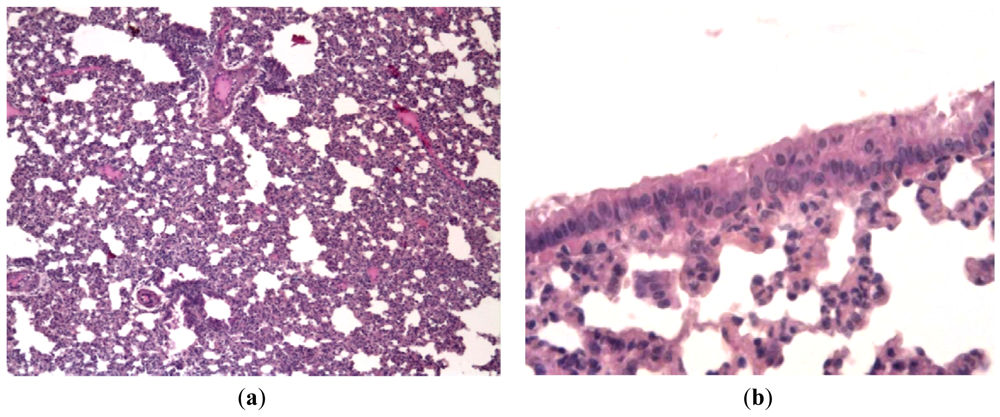

Infecting of Syrian hamsters with human parainfluenza virus (hPIV) results in non- fatal mild bronchitis, bronchiolitis and pneumonia. The virus can be recovered from the lungs on day 3 p.i., and specific tissue damage can be observed on day 7.

Hamsters infected with hPIV showed no observable evidence of illness prior to sacrifice, but histologically there was consistent production of pneumonia. Lung lesions consisted of scattered endobronchial exudates composed of mononuclear and polymorphonuclear cells, peribronchial and perivascular round cell infiltrates, and wide areas of interstitial pneumonia. Bronchial epithelium had a specific appearance containing groups of tall giant cells protruding into the bronchial lumen [Figures 5(a,b)]. Animals treated with Ingavirin and ribavirin demonstrated almost normal lung tissue architecture with few infiltrating cells [Figures 5(c,d)].